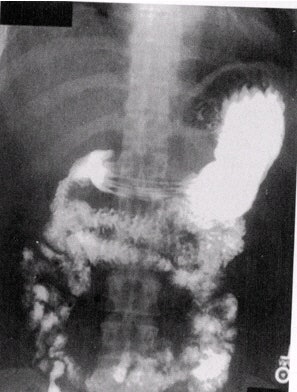

![]() |

| Single-contrast UGI overhead PA film. Note that the stomach is imaged at the superior aspect of the film so as to visualize as much of the small bowel as possible. Image courtesy of Dr. Naveed Ahmad. |